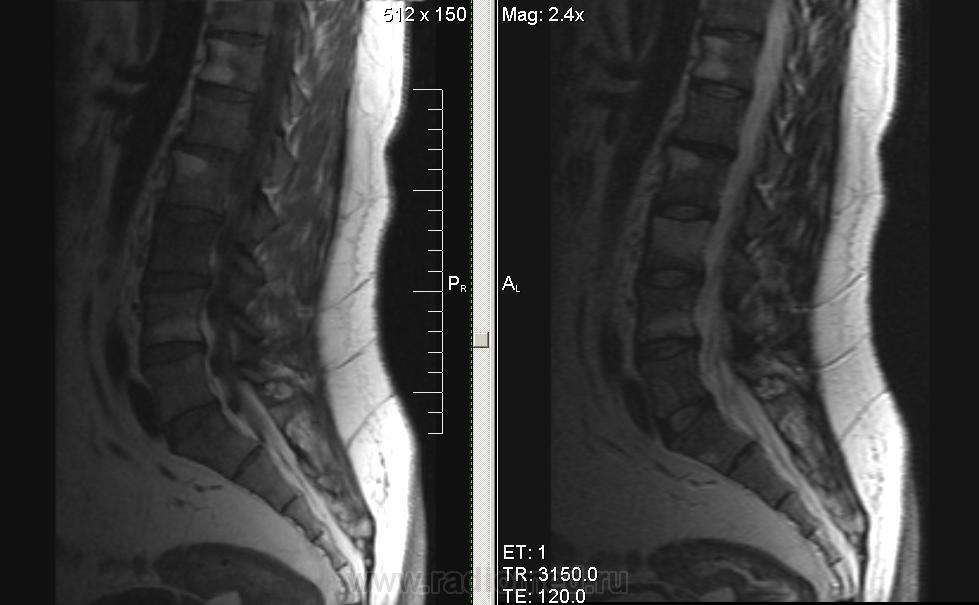

Мужчина, 1974г.р. В течении полугода боли в правой ноге, пояснице. Коллеги, подскажите, пожалуйста, что за системная болячка такая. В грудном отделе - то же самое.

серонегативная спондилоартропатия (?)

Ага, по ссылке Бехтерева.. Тока обычно изменения в области дугоотростчатых суставов и рёберно-позвонковых. У меня было первой мыслью, но суставов на представленных снимках нет.

Сакроилеит. Так что спондилоартрит наиболее вероятен. И боль в правой ноге понятна. Я если у молодых людей причины для корешковых болей не вижу, делаю программу на крестцово-подвздошные суставы. Единственно, в позвоночнике обычно бывает отёк костного мозга апофизов, дугоотростчатых и рёберно-позвонковых суставов.